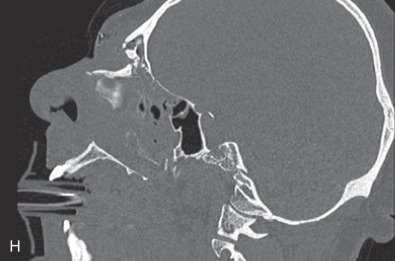

The gold standard for radiographic evaluation is thin-slice helical computed tomography (CT). Midface fractures are confirmed by axial, coronal, and sagittal views. The degree of comminution, bone loss, and detailed images of the fracture patterns can be assessed and juxtaposed to surrounding soft tissue structures. 3D reconstruction, when utilized, can aid in visualizing the complex 3D anatomical orientation of fracture fragments that occur in Le Fort injuries and facilitate reconstructive planning.

Le Fort II fractures are pyramidal in shape, involving the central portion of the midface while the lateral orbits and zygoma remain intact. The line of fracture extends bilaterally through the nasofrontal junction, medial orbital wall, inferior orbital rim, along the maxilla, through the dental alveolus anteriorly and posteriorly at the level of the maxillary tuberosity into the pterygoid plates ( Figs. 1.13.14 and 1.13.15 ). Only Le Fort II fractures violate the inferior orbital rim, causing the highest incidence of infraorbital nerve hypesthesia due to the proximity to the infraorbital foramen. Bones of the maxilla below the Le Fort II line of fracture can be intact, however they are often comminuted with other fracture patterns occurring in the Le Fort II segment. The force is typically delivered centrally at the level of the nasal bones, resulting in the separation of the central maxilla from the surrounding facial skeleton. Brain injuries are more frequent in central Le Fort II injury patterns.